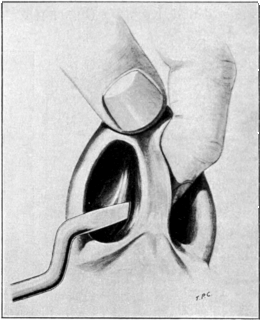

| 41. | Sims’s Operation for the Repair of a Vesico-vaginal Fistula | 136 |

| 42. | Simon’s Operation for the Repair of a Vesico-vaginal Fistula | 136 |

| 43. | Repair of a Vesico-vaginal Fistula by Dédoublement | 137 |

| 44. | Repair of a Vesico-vaginal Fistula. Sims’s Operation | 137 |